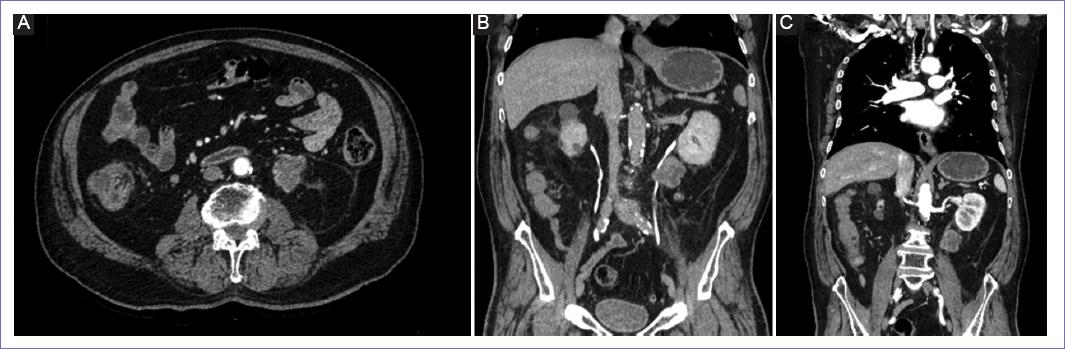

Comienza su padecimiento en noviembre del 2021 con presencia de dolor testicular, así como aumento de tamaño del testículo, por lo que acude a atención a medio particular en enero del 2022, donde le comentan que se trata de un tumor testicular que requiere intervención quirúrgica, por lo que esta se lleva a cabo; según se comenta, sin complicaciones. No obstante, en el resultado de patología se reporta neoplasia fusocelular mesenquimal de alto grado de cordón espermático de 9 × 7 cm, con invasión linfovascular presente, así como margen quirúrgico proximal positivo, por lo que es enviado al Instituto Mexicano del Seguro Social en marzo del 2022, donde es valorado por el servicio de oncología médica y radiooncología, y se otorga tratamiento adyuvante con seis ciclos de vincristina 1.6 mg, doxorubicina 60 mg y ciclofosfamida 1,600 mg (concluyendo en agosto del 2022), así como radioterapia inguinal y paratesticular con 36 Gy en 18 fracciones (concluyendo en octubre del 2022), posteriormente envían al servicio de cirugía oncológica para continuar con vigilancia. Durante esta con adecuada evolución, manteniéndose asintomático, con periodo libre de enfermedad de 2 años con 4 meses, hasta que en estudio tomográfico de control en enero del 2025 se observa tumor a nivel de retroperitoneo, en lecho de riñón izquierdo en contacto con grasa perirrenal, así como uréter izquierdo desde tercio proximal y medio (Fig. 1), sin evidenciar actividad a distancia.

Figura 1 A: tomografía axial de abdomen en fase contrastada con presencia de tumor retroperitoneo con afectación de uréter izquierdo. B y C: imágenes coronales por tomografía abdominal contrastada donde se evidencia tumor en retroperitoneo con afectación de uréter izquierdo hacia pelvis renal izquierda.